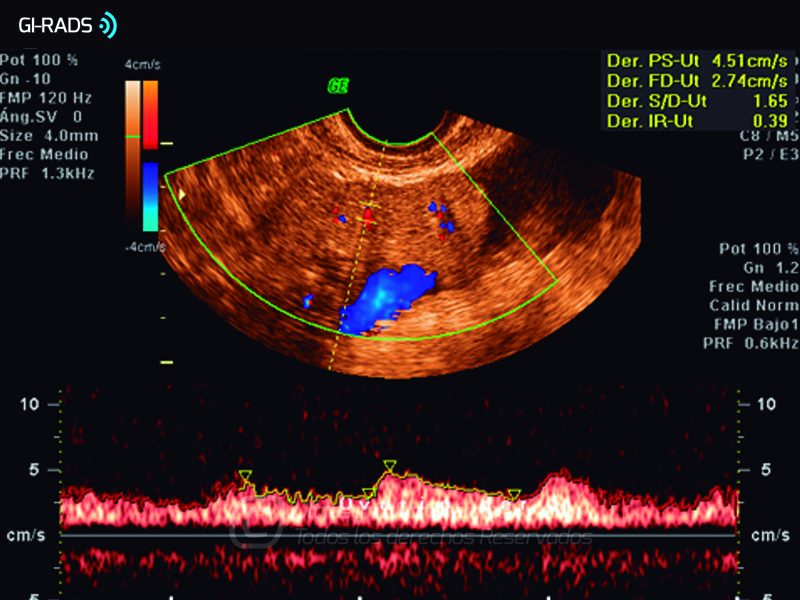

Cáncer Anexial – Baja Resistencia

• Cáncer Anexial – Baja Resistencia